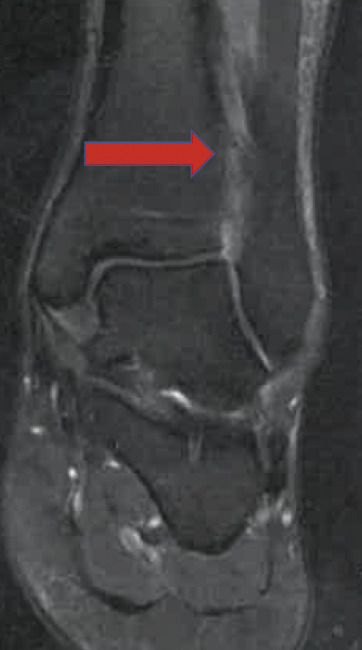

Une IRM confirme l’entorse grave dite « de la syndesmose », avec rupture complète du ligament tibiofibulaire antéro-inférieur (LTFAI) et de la membrane interosseuse (fig. 2 et 3 ), mais le ligament tibiofibulaire postéro-inférieur (LTFPI) est intact. L’absence de diastasis tibiofibulaire au bilan radiologique complémentaire classe la lésion en stade 2 (fig. 4).

Une IRM confirme l’entorse grave dite « de la syndesmose », avec rupture complète du ligament tibiofibulaire antéro-inférieur (LTFAI) et de la membrane interosseuse (